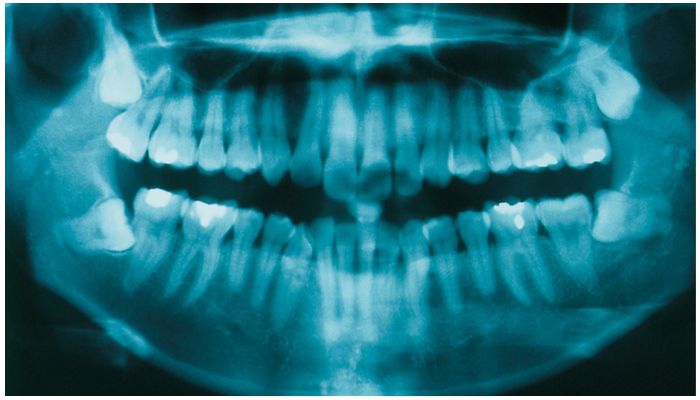

Удалять четверки необходимо подросткам и взрослым пациентам, у которым скученность зубов вызвана анатомическими особенностями челюсти. При узкой кости и больших молярах происходит сдвиг клыков и резцов. В результате отдельные элементы искривляются, наслаиваются друг на друга и выбиваются из ровного ряда. Если вернуть на место выпирающие части невозможно, с удалением тянуть не стоит. Определить необходимость данного вмешательства можно по снимку, который выполняется для всех пациентов до и после установки корректирующей системы.

Каждый случай ортодонт и челюстно-лицевой хирург рассматривают индивидуально. Какие единицы попадают в зону риска, специалисты решают на основании анамнеза и собранных результатов предварительного обследования.

Обычно для установки брекетов удаляются четыре зуба — два верхних и два нижних премоляра. Это делается для создания необходимого пространства для выравнивания зубов и коррекции прикуса.